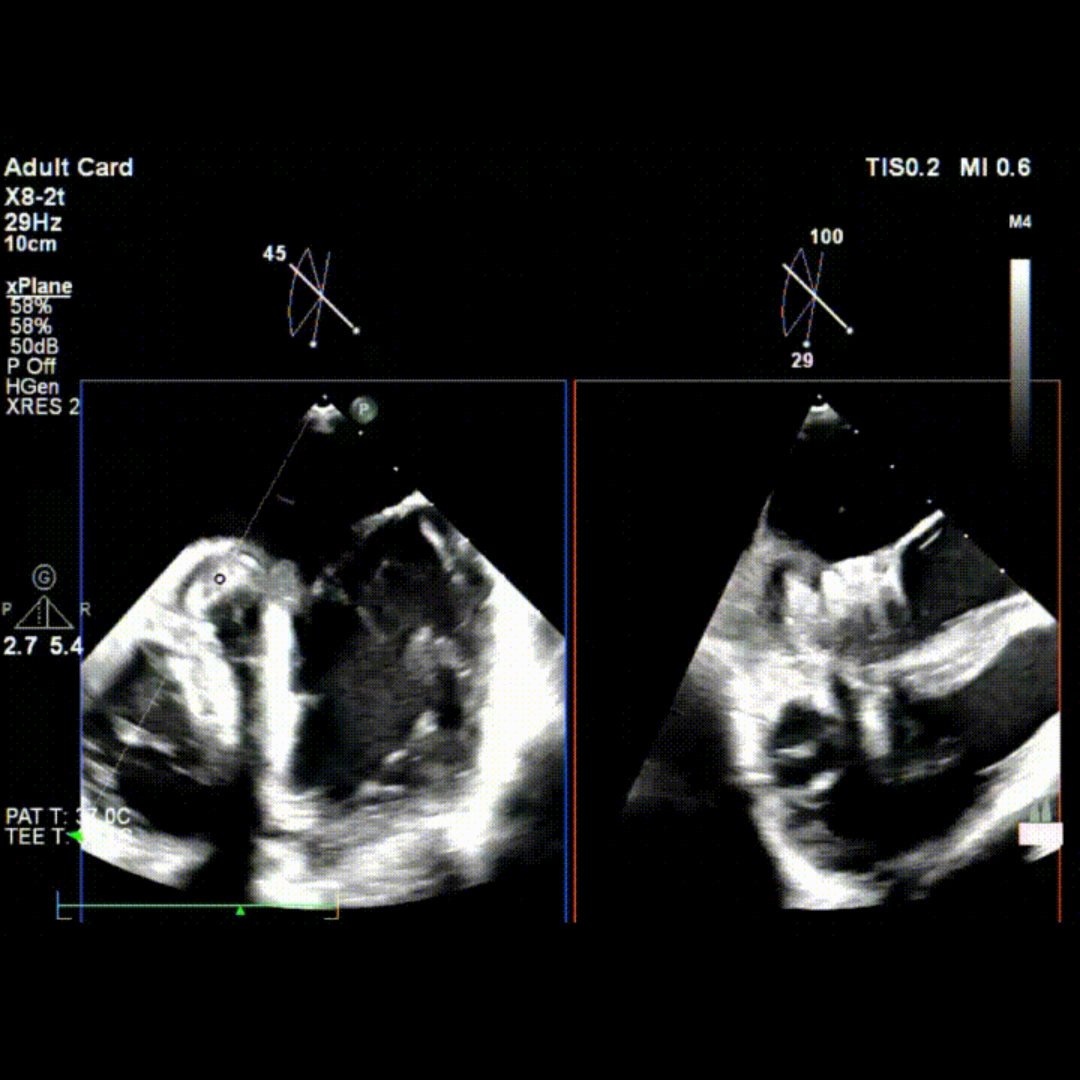

会议期间,张海波教授团队联合李伟教授完成了一例TA-TEER现场手术演示。患者为混合性二尖瓣反流(DMR+FMR),伴瓣环扩大、前瓣叶冗长、三区反流、后叶栓系及短小等复杂情况。术者在充分评估后选择置入双夹,手术获得圆满成功。现场专家就夹子型号选择、双夹放置位置及三区交界病变穿刺点等问题展开了深入讨论。

术前TEE影像

术中TEE影像